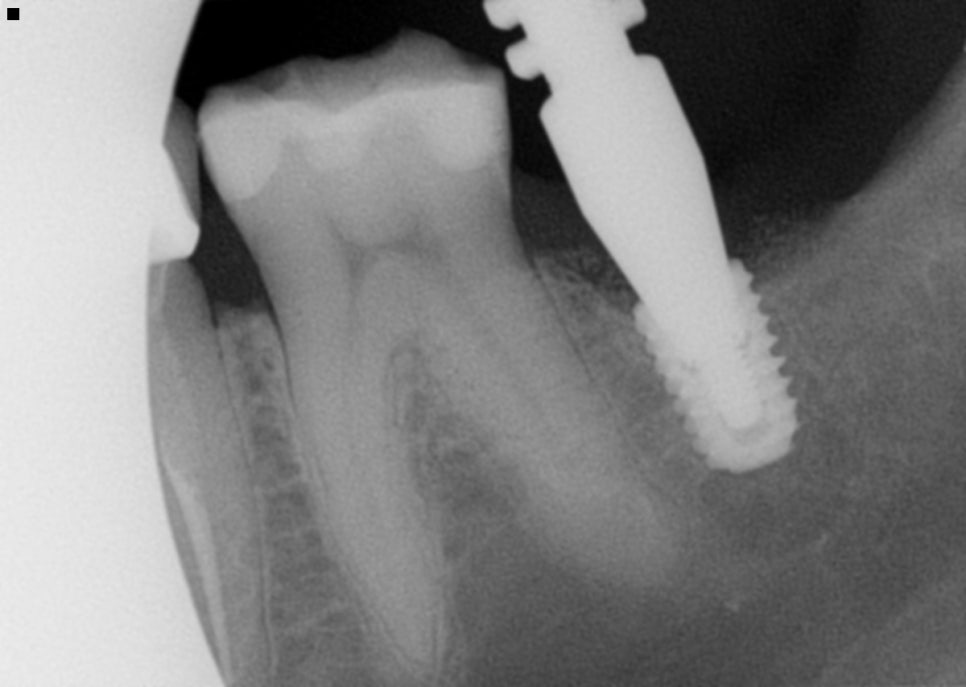

두 달 뒤 픽스쳐 레벨 인상채득 및 상태점검

경과를 보기 위해 내원을 하셨는데요.

경과만 보러 온 게 아닌 픽스쳐 레벨

인상채득차 경과차 방문을 하셨습니다.

임플란트 픽스쳐(뼛속에 식립된 본체의 위치)를

정확하게 본뜨기 위한 인상채득 방법인데요.

뼛속에 식립된 본체에 인상용 부품을 연결해서

입안에서 본을 뜨면

픽스쳐 위치와 방향이 복제가 됩니다.

이 기준을 가지고 보철물을

정밀하게 제작하게 됩니다.

ISQ 측정을 진행했는데 임플란트와 뼈가

얼마나 잘 붙어있는지 고정력 체크를 하는데

전용 장비가 있습니다.

진동으로 체크를 하여 안정도 수치를

확인할 수 있어 이를 보고

임플란트 경과를 확인이 가능합니다.

또한 치근단 촬영을 진행해 치아 전체적으로

주변 뼈를 자세히 촬영하여

여러 상태 확인을 합니다.

픽스쳐의 위치, 골유착여부, 보철물 체결 상태,

피개나 파절 여부를 확인했습니다.